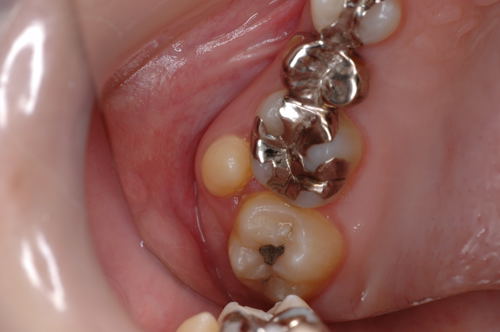

| 歯根破折の症例です。時々歯肉が腫れて痛む、咬むと痛いという症状があります。虫歯も無いのにおかしいなと思ったら、歯が割れていたなんて事があります。レントゲン写真で分かる場合もありますが、抜歯して初めて分かる場合もあります。元々健康な歯でも割れる事もありますので、硬い食べ物には気を付けましょう。 | ![]() ![]() ![]() ![]() |